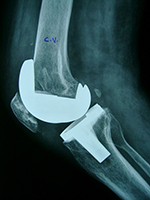

OA - CASE 4

c vora